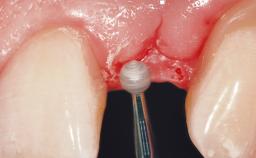

Immediate Placement of an Implant in a Maxillary Left Central Incisor Site

A 33-year-old female patient presented with an upper left central incisor that required extraction after a failed endodontic therapy. The tooth had been traumatized when the patient was a teenager and had undergone several endodontic treatments, including two apicectomy procedures. The patient was in good health and did not smoke. Clinical examination showed that the patient had a high lip line. In full smile, the gingival margins of the upper teeth were visible to the first molars. The gingival margins of central incisors 11 and 21 were only just showing. Examination of tooth 21 confirmed that the tooth was mobile and had hypererupted by 1 mm.

Placement Protocol Immediate implant placement

Tooth Site Maxillary incisor or canine

Socket Morphology Single-root socket